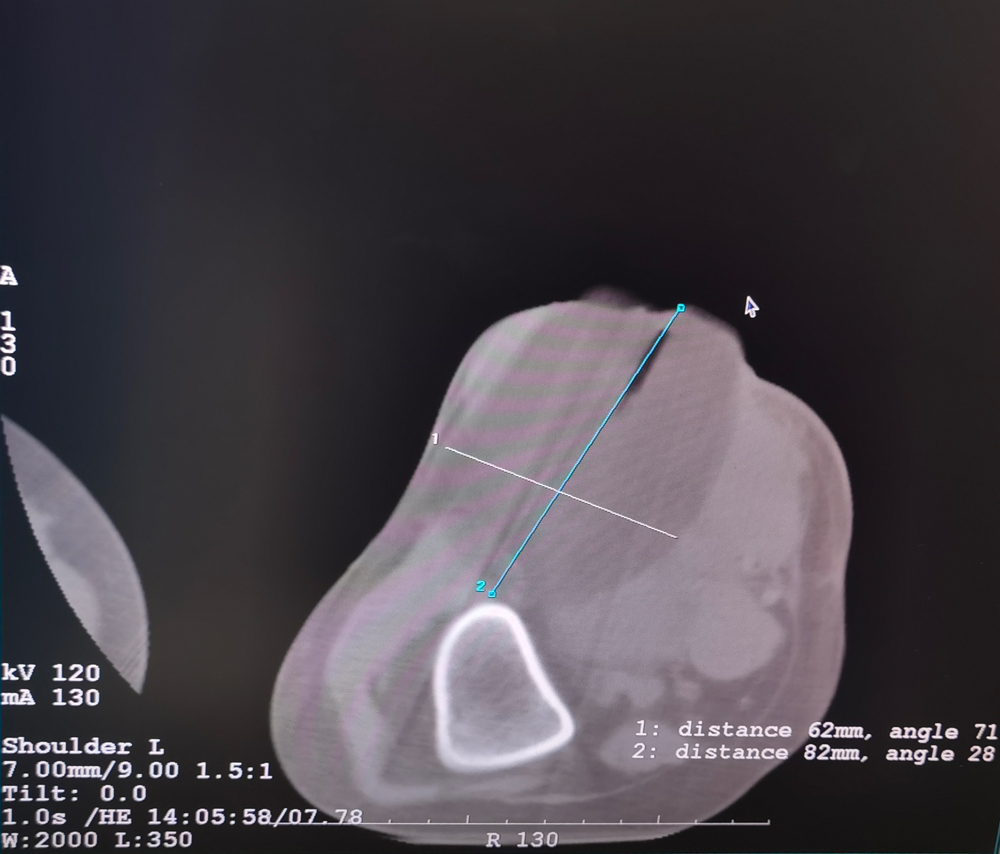

女,42歲,復(fù)發(fā)性脂肪瘤,病灶位于右側(cè)膝關(guān)節(jié),直徑大小13cm。采用雙針?lè)桨福策M(jìn)行6個(gè)凍融循環(huán),最大冰球直徑達(dá)8.2cm,術(shù)中多方位治療全面覆蓋病灶范圍。患者術(shù)后狀況良好。